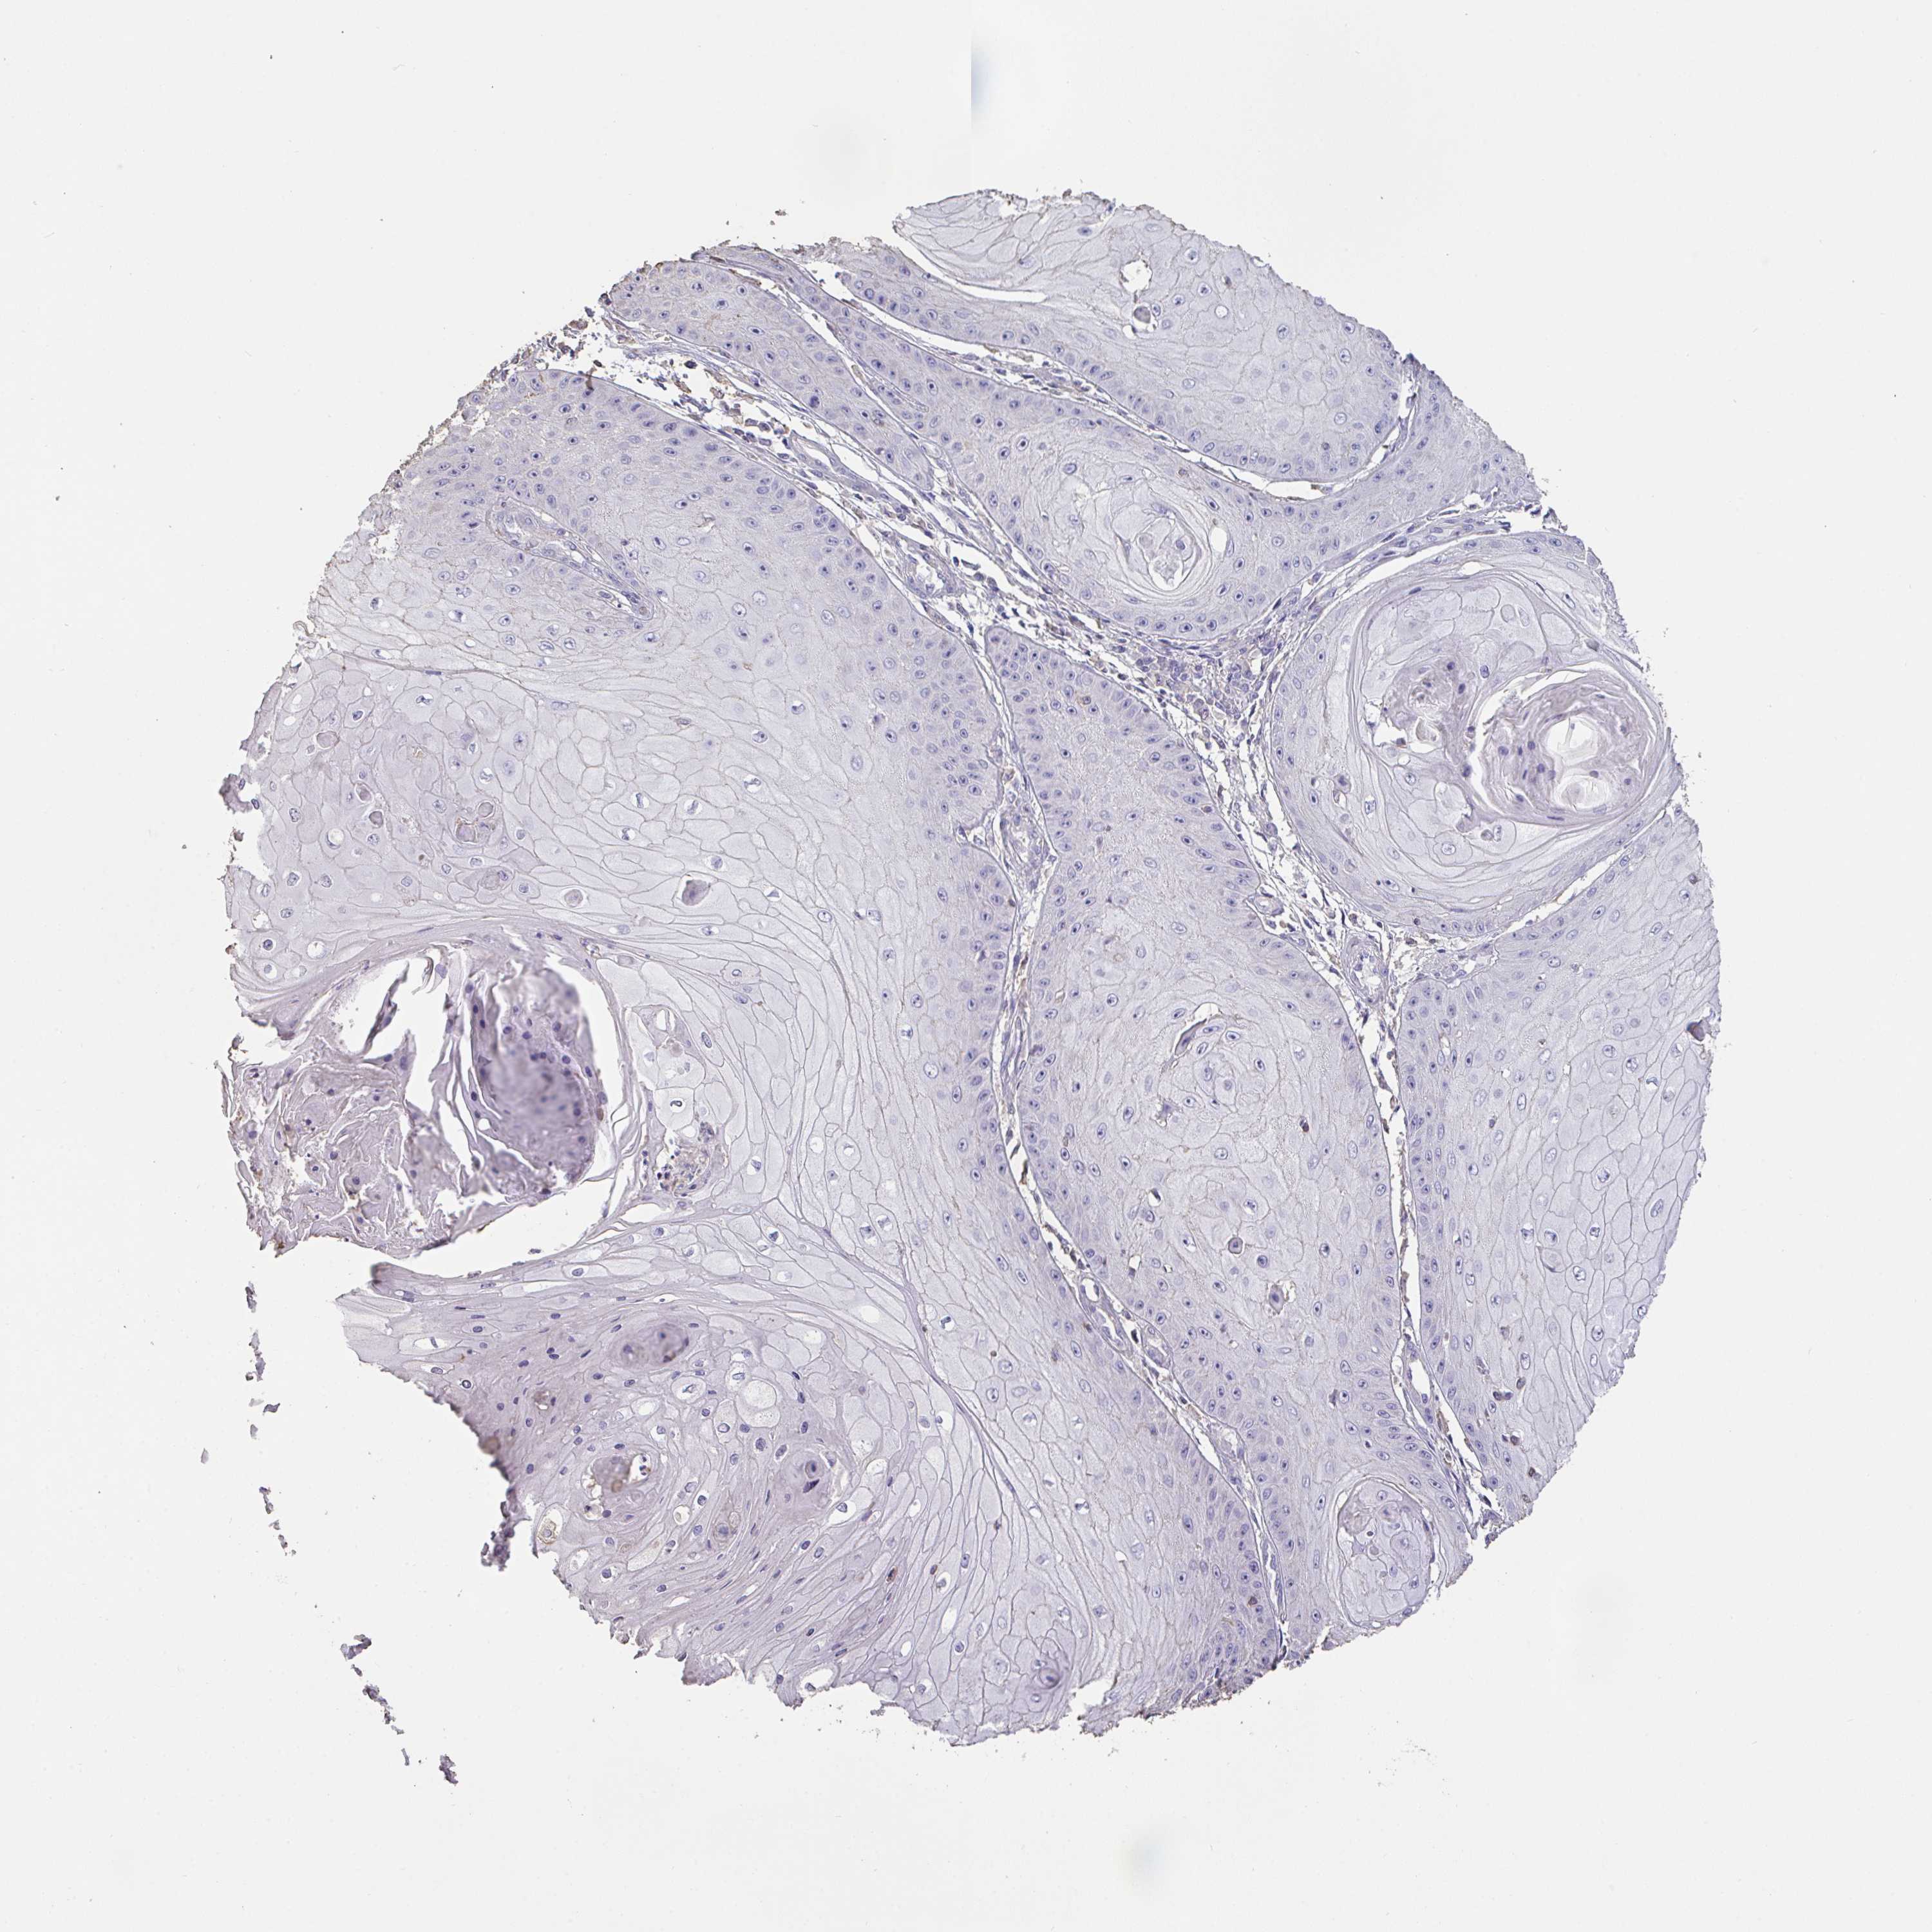

CANCER SKIN CANCER Show tissue menu

Basal cell and squamous cell cancer

SKIN CANCER - Protein expressioni

A mouse-over function shows sample information and annotation data. Click on an image to view it in a full screen mode. Samples can be filtered based on level of antibody staining by selecting one or several of the following categories: high, medium, low and not detected. The assay and annotation is described here.

Each image is clickable and will lead to virtual microscopy that enables deeper exploration of all samples and also displays staining intensity scores, fraction scores and subcellular localization as well as patient and tissue information for each sample.

Antibody HPA056427

Basal cell carcinoma

Squamous cell carcinoma, NOS